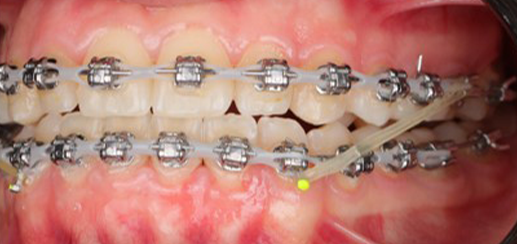

Initial leveling in the maxillary arch was carried out with a 0.014 CuNiTi archwire. This was followed by a 0.018 CuNiTi wire, with stoppers positioned mesial to the molars and activated to provide protrusion of incisors. The mandibular arch was then bonded and initial alignment was achieved with a 0.014 CuNiTi wire, then both jaws are progressing to 0.014 × 0.0275 CuNiTi and subsequently 0.018 × 0.0275 CuNiTi for torque control.

Finishing was completed with a 0.018 × 0.0275 TMA archwire in conjunction with Class III elastics.